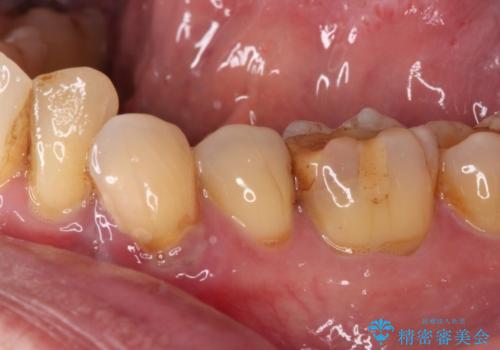

検査で見つかった虫歯 セラミッククラウンでの治療

担当医 岡田康成